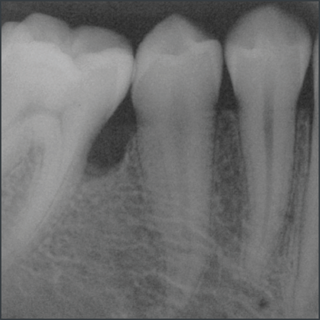

20 years after treatment with Straumann® Emdogain®.

Courtesy of Prof. Carlos Nemcovsky